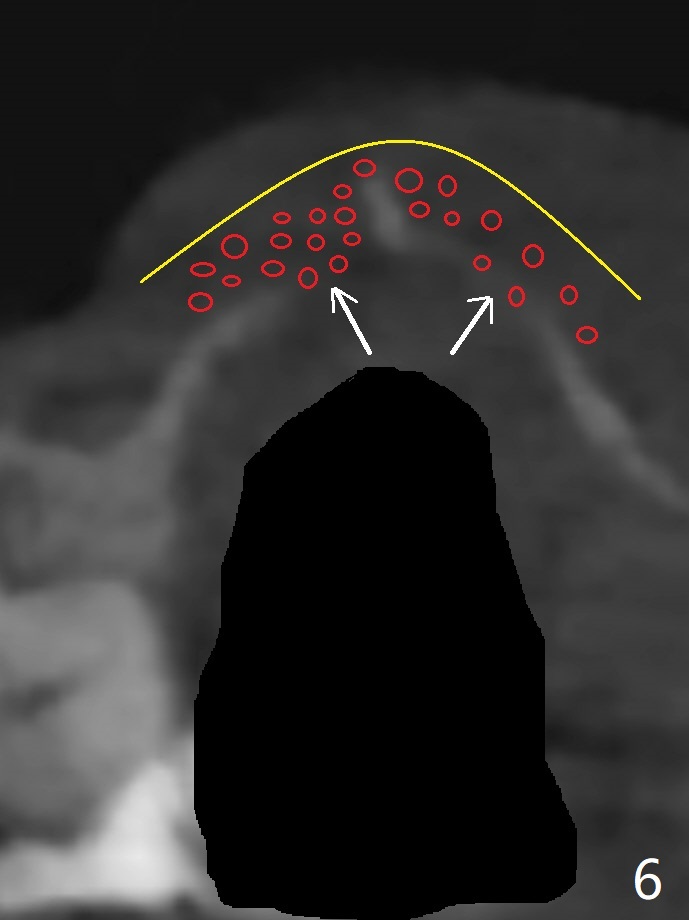

59岁女右上七骨质吸收严重(图一),上颌窦底板薄(图二:*),而窦膜厚(图三:*),应该容易提升,腭侧根吸收(图四:P),上颌窦底板穿孔(图五:*),拔牙后(图六:黑色),水提升(白箭头),放置PRF膜(黄色曲线)和粘性骨块(红色圆圈),最后完成位点保留(图七:大圆圈),放置另外一块PRF膜和6个月吸收膜,缝合,牙周或者树脂敷料。Return to No Deviation 19-21 位点保留后 导板与张口度 Xin Wei, DDS, PhD, MS 1st edition 09/09/2020, last revision 01/01/2021